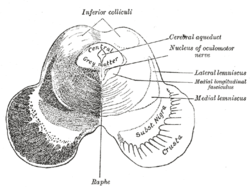

Schematic representation of the chief ganglionic categories (I to V). Transverse section of mid-brain at level of inferior colliculi.

Transverse section of mid-brain at level of inferior colliculi. Transverse section of mid-brain at level of superior colliculi.